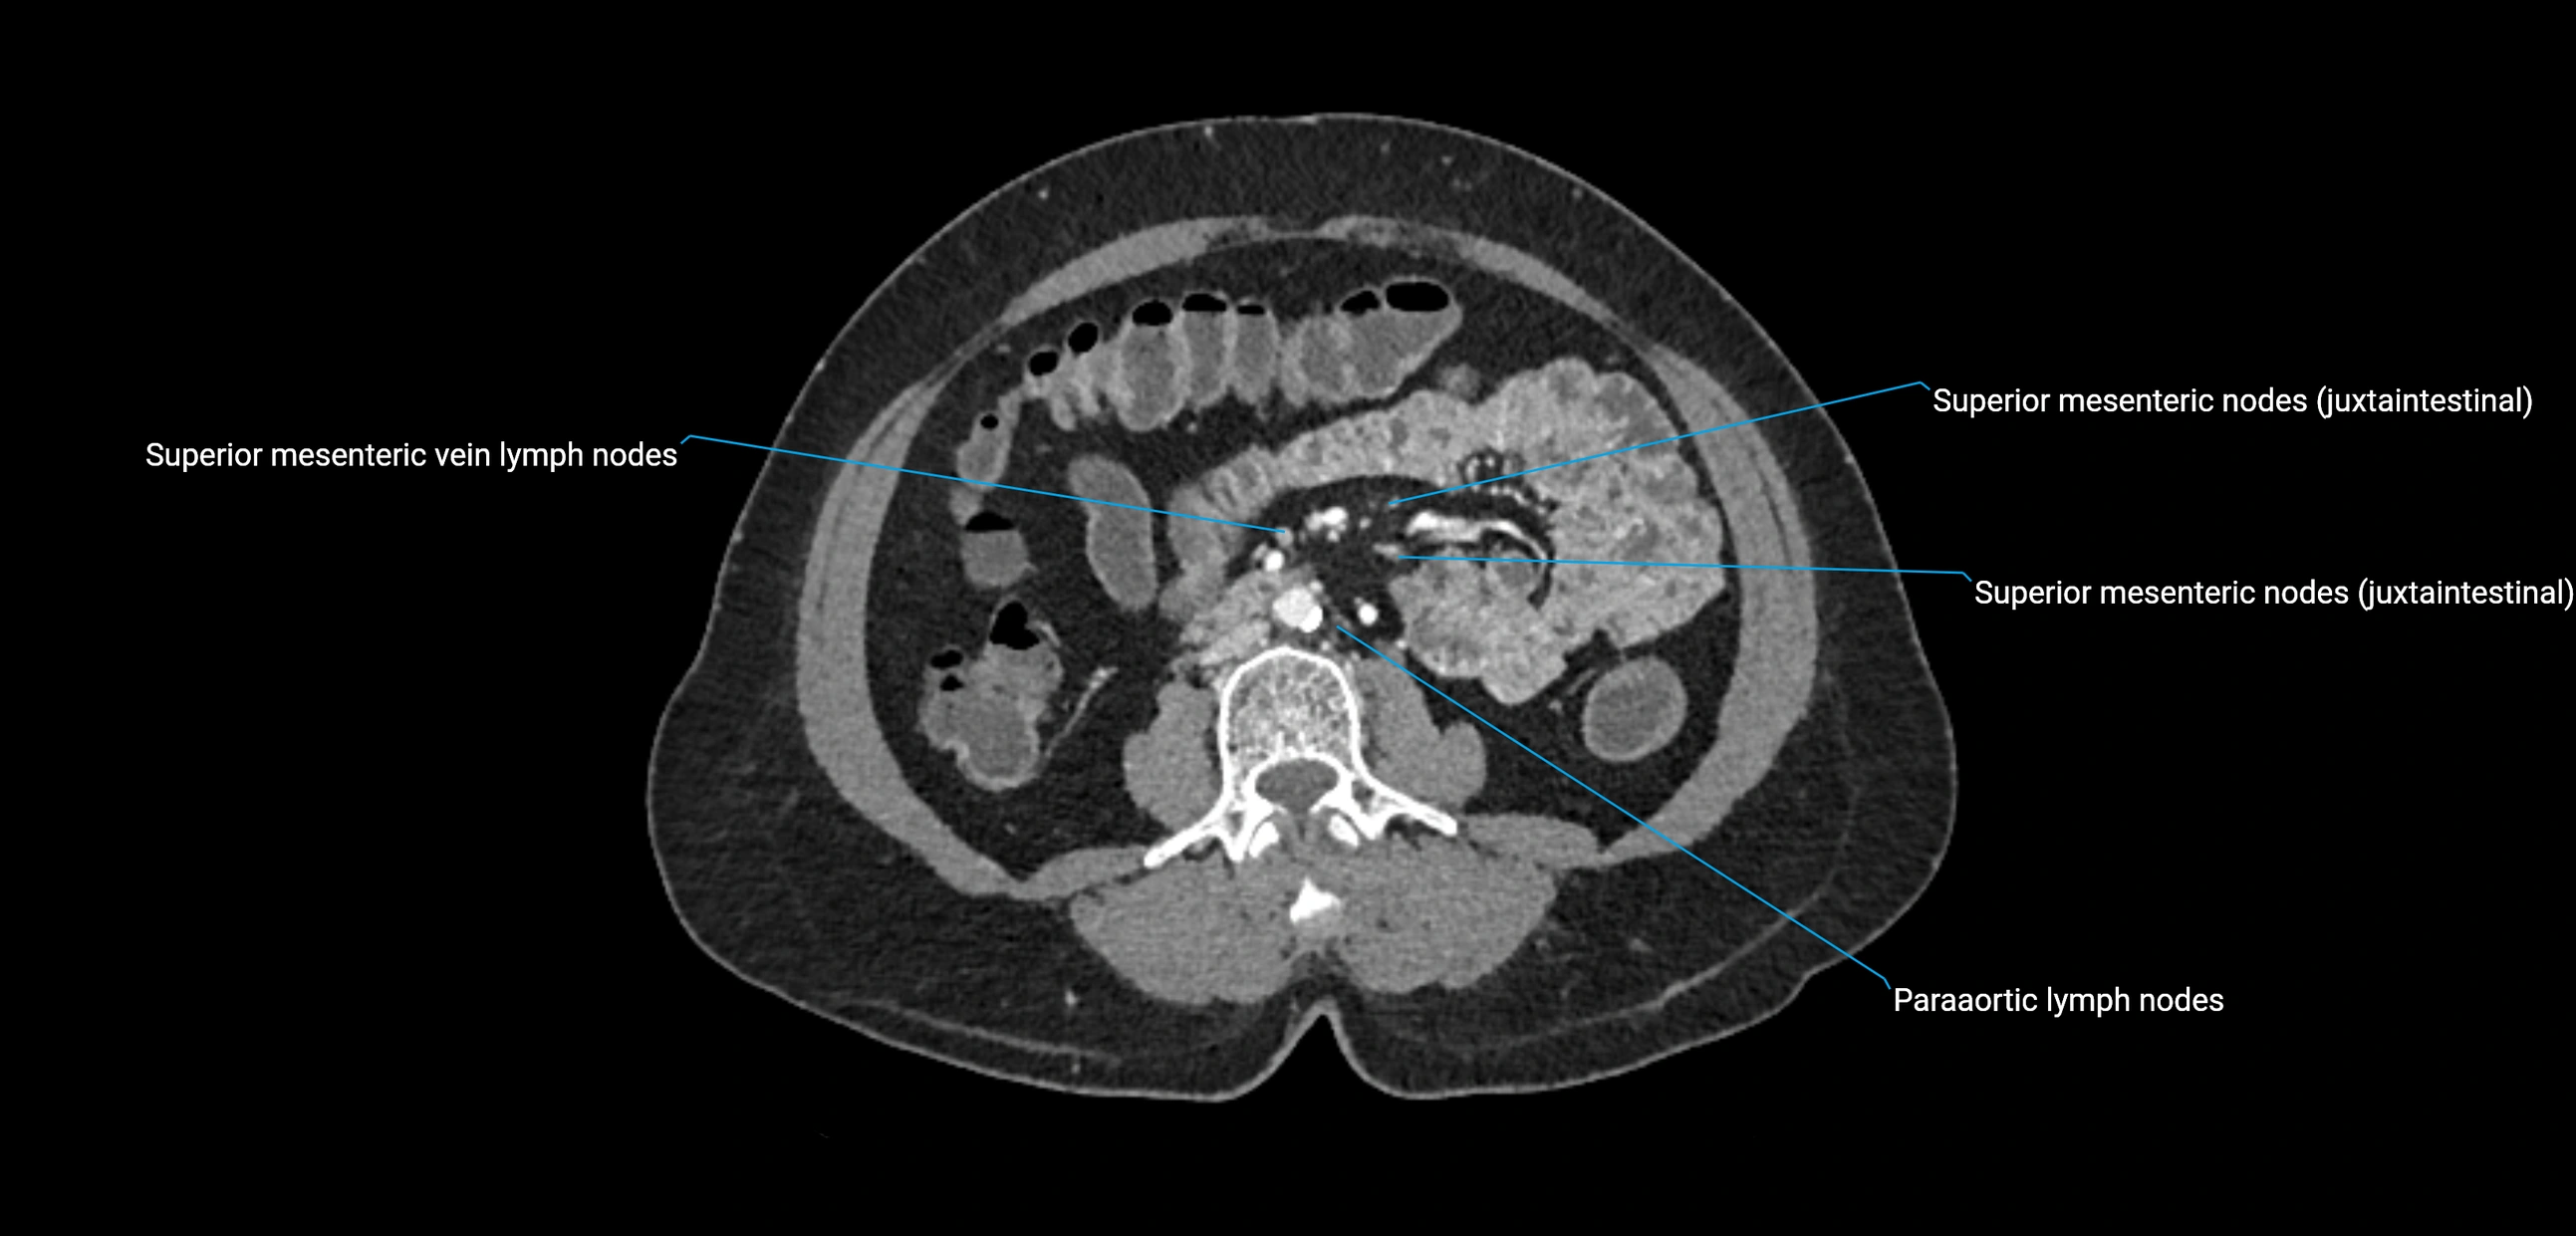

CT Appearance

CT Pre-Contrast:

• Nodes appear as soft-tissue density nodules adjacent to the aorta and IVC

• Calcification may be seen in chronic infections (e.g., tuberculosis)

CT Post-Contrast:

• Normal nodes enhance homogeneously

• Malignant nodes may show heterogeneous enhancement, central necrosis, or conglomerate formation

• Size >1 cm short axis is suspicious, though morphology and distribution are equally important

CT image

image